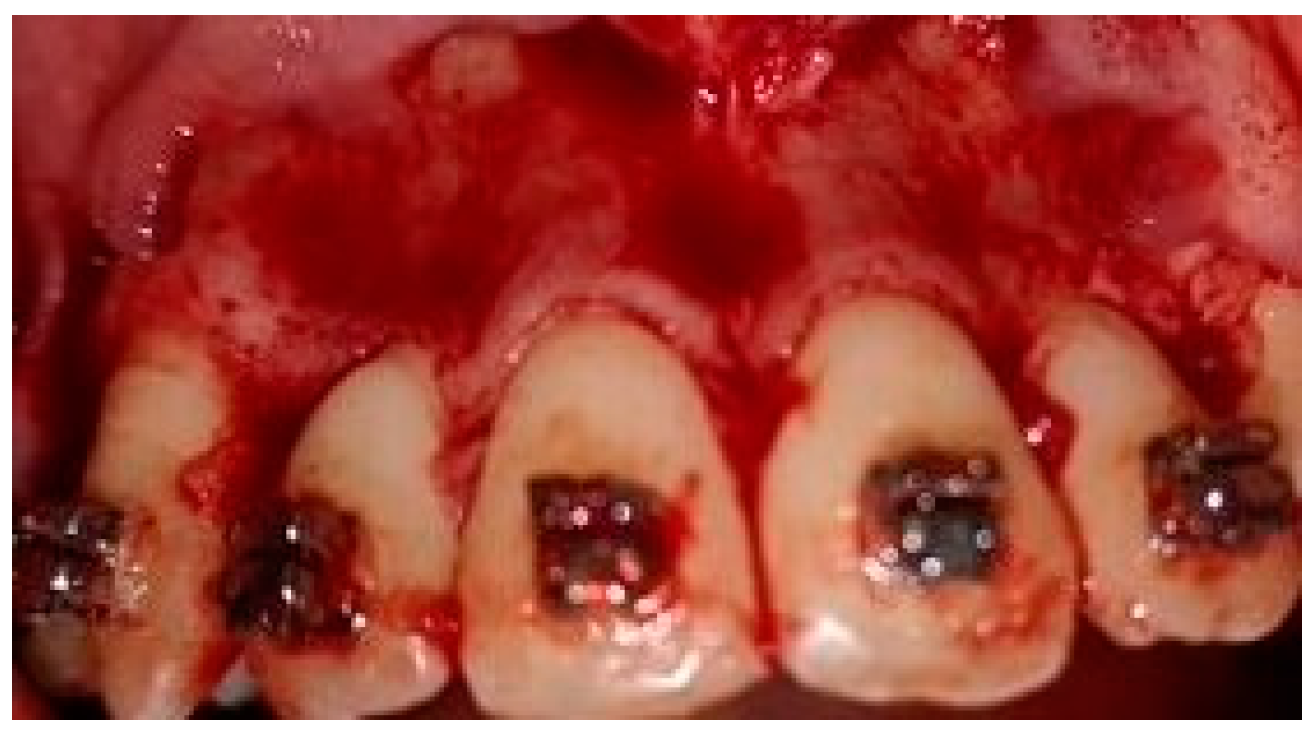

2.5. Surgical Phase